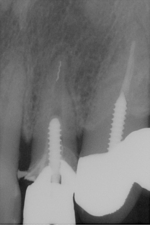

根管治療レッジ除去リカバリー症例

術前 ➡

術中

根の先に影(感染)が出てしまい根の治療を行わないといけないのですが以前他院にて処置を施した古い薬が入っています

画像を見ると手前の根にはしっかりと先まで薬が入っていません(1枚目の画像)

根のカーブに対応できず間違った方向へ削り込んでしまっています(赤矢印)

古い薬を除去しとあるテクニックを駆使し正しい根幹への道を見つけました(青矢印)

簡単にやっているように見えますがそのまま器具を入れては大きく間違った道に導かれてしまうなか、その脇から1mmにも満たない狭く曲がった孔を探しそちらへ導くのは至難の技ですが、マイクロスコープとCTを使いしっかりとした手法で行うとこのような症例にも対応できます